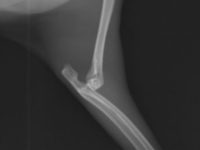

ウサギ 2026年2月22日 ウサギの肘関節脱臼 この子は前足を脱臼してしまい、かかりつけ医では処置できないとのことで当院に来院されました。 右前肢が動かなくなっており、レントゲン検査を行うと、 このように右前肢の肘関節が脱臼しています。 治療にはいくつか方法があります […]